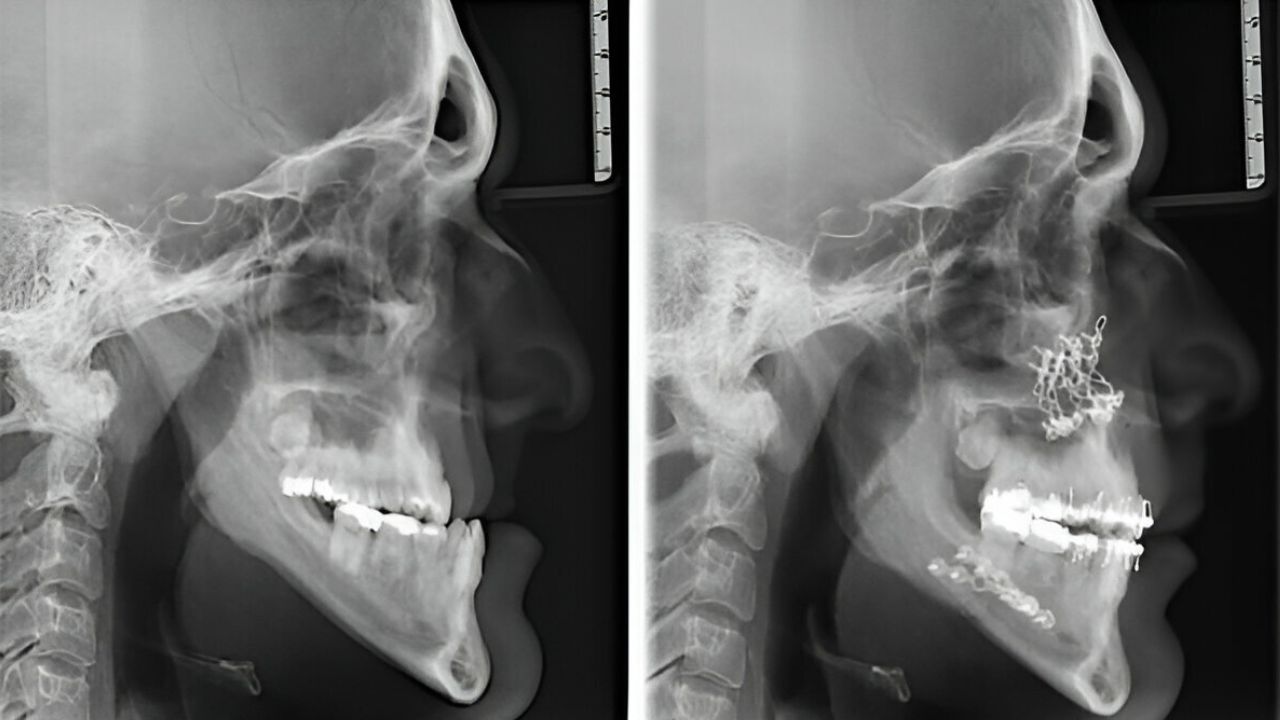

Cirurgia Ortognática antes e depois: conheça os resultados!

A cirurgia ortognática é um procedimento cirúrgico que visa corrigir desalinhamentos faciais e maxilares, proporcionando melhorias estéticas e funcionais significativas. Neste artigo, exploraremos o processo